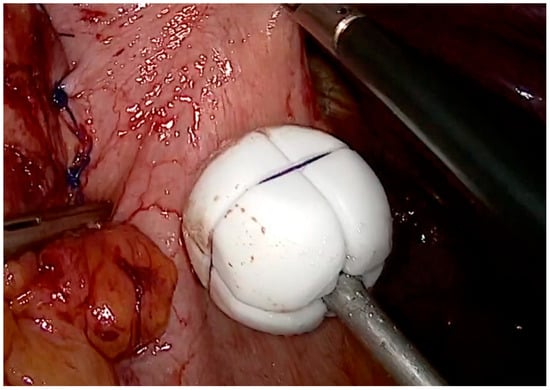

19. RefluxStop™